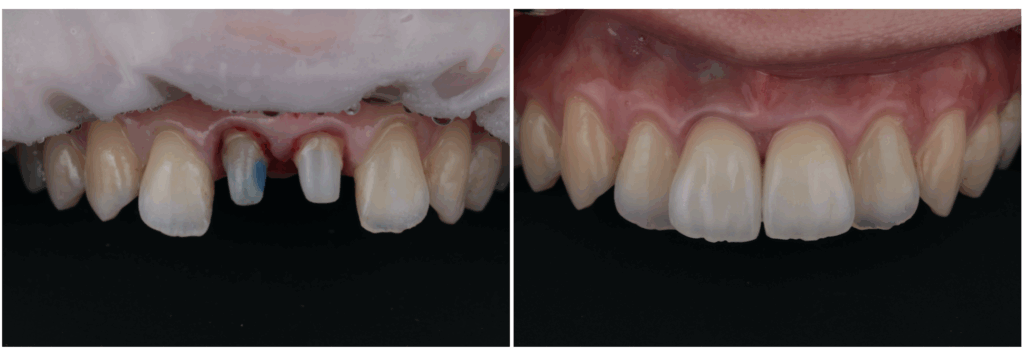

歯の白濁が気になる方へ|削らずに改善を目指す「ICON(アイコン)治療」

最近、「歯の白濁が気になる」「前歯の白い斑点が目立って笑いづらい」と感じていませんか?鏡を見たときや写真に写った自分の歯を見て、違和感を覚えたことがある方は意外と多いものです。歯の白濁は痛みがないことがほとんどですが、見た…